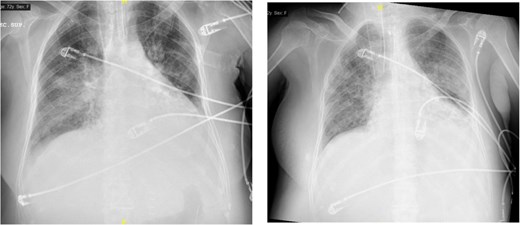

Around 36 h post-surgery, the patient developed sudden acute respiratory failure requiring escalating doses of norepinephrine. Imaging studies revealed bilateral interstitial infiltrates consistent with a differential diagnosis of ARDS or acute pulmonary oedema (APE) (Fig. 1). Despite broad-spectrum antibiotics and respiratory support, progressive hemodynamic deterioration ensued, prompting surgical re-exploration. Laparotomy revealed patchy intestinal ischemia likely secondary to multiorgan failure (MOF), culminating in the patient’s death. Autopsy findings revealed systemic endothelial damage with calcium deposition resembling ischemia–reperfusion injury without evidence of sepsis.

(A, B) Differences between the chest X-ray in the immediate postoperative period and at 36 h after the onset of respiratory failure. (C) The chest CT confirms pulmonary exudates compatible with ARDS (acute respiratory distress syndrome).